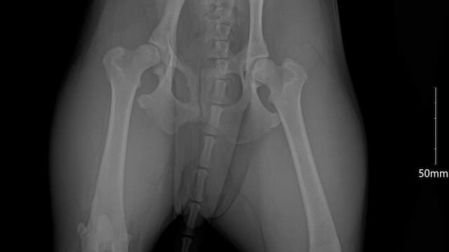

De inmediato los vecinos la rescataron y la llevaron al veterinario, ha recibido atención médica, sus lesiones son valoradas por medio rayos “X”, ultrasonido y esta medicada, cuya suma se ha elevado y piden apoyo para pagar los gastos

El veterinario les comentó que presenta luxación coxofemoral, es decir luxación de cadera, una condición dolorosa y limitante, ocurre cuando la cabeza del fémur, el hueso del muslo, se separa de su cavidad natural en la pelvis, lo que puede presentar complicaciones a largo plazo si no se aborda de manera oportuna y adecuada.